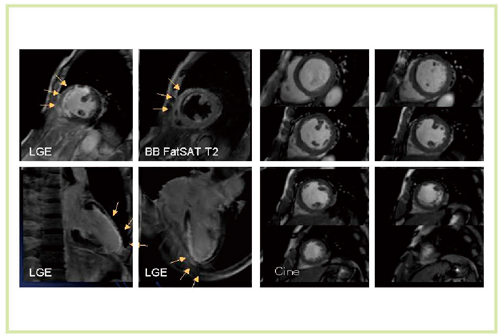

3T MRIによる心臓は,susceptibility artifactの影響やSAR(specific absorption rate)の制約のために,従来は撮像が困難な領域であった。しかし,Titan 3Tでは非常に明瞭な画像が得られている(図5〜8)。

図5 急性心筋梗塞症例(60歳代,男性)のT2強調画像 (脂肪抑制black blood TSE)(Titan 3T) SNRや浮腫心筋,正常心筋のCNRが向上

図5 急性心筋梗塞症例(60歳代,男性)のT2強調画像

(脂肪抑制black blood TSE)(Titan 3T)

SNRや浮腫心筋,正常心筋のCNRが向上